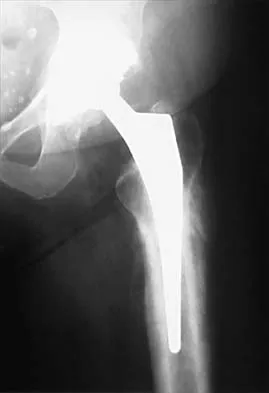

Figure 10 shows the AP radiograph of an ambulatory 76-year-old patient. What is the most appropriate surgical treatment option for this patient?

The patient has a periprosthetic fracture around a loose cemented femoral component. The proximal bone stock is poor; therefore, this fracture may be categorized as Vancouver 3-B. Hip arthrodesis and resection arthroplasty provide suboptimal results, particularly for ambulatory patients. Although impaction allografting may be an option to restore the bone stock in a younger patient, the latter procedure will be very difficult to perform when the proximal bone is poor in quality and fractured. Cementing another component into this wide femur is not an option. The best option for revision of the femoral component in this elderly patient is proximal femoral replacement arthroplasty. Malkani AL, Settecerri JJ, Sim FH, et al: Long-term results of proximal femoral replacement for non-neoplastic disorders. J Bone Joint Surg Br 1995;77:351-356.